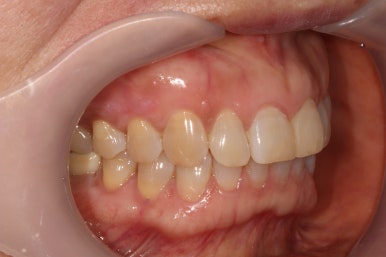

앞면, 양쪽 옆면 모두 아주 깔끔하게 유지되고 있네요!

기억하고 있으실지 모르겠지만, 전반적으로 나타내고 있던 잇몸의 붉은색도 대부분 사라져 있는 상태입니다.

임플란트 또한 적절히 유지되고 있고 잘 사용하고 계신 상태입니다.

신경치료와 지르코니아 크라운 치료를 받았던 치아도 뿌리끝 염증 없이 잘 사용중이시구요!